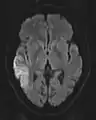

ADC image

ADC image of the same case of cerebral infarction as seen on DWI in section above

An apparent diffusion coefficient (ADC) image, or an ADC map, is an MRI image that more specifically shows diffusion than conventional DWI, by eliminating the T2 weighting that is otherwise inherent to conventional DWI.[24][25] ADC imaging does so by acquiring multiple conventional DWI images with different amounts of DWI weighting, and the change in signal is proportional to the rate of diffusion. Contrary to DWI images, the standard grayscale of ADC images is to represent a smaller magnitude of diffusion as darker.[23]

Cerebral infarction leads to diffusion restriction, and the difference between images with various DWI weighting will therefore be minor, leading to an ADC image with low signal in the infarcted area.[24] A decreased ADC may be detected minutes after a cerebral infarction.[26] The high signal of infarcted tissue on conventional DWI is a result of its partial T2 weighting.[27]